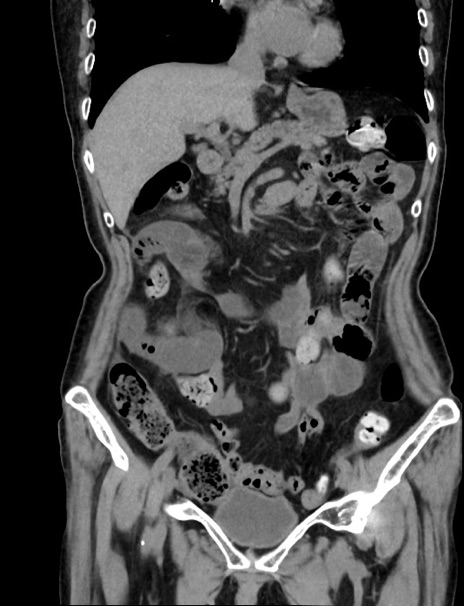

症例33(冠状断像)

【症例】70歳代 女性

【主訴】心窩部痛

【現病歴】延髄病変の精査・加療にて神経内科入院中。本日より心窩部痛あり。

【既往歴】虫垂炎

【身体所見】右下腹部を中心に圧痛と反跳痛あり。

【データ】WBC 10900、CRP 0.02